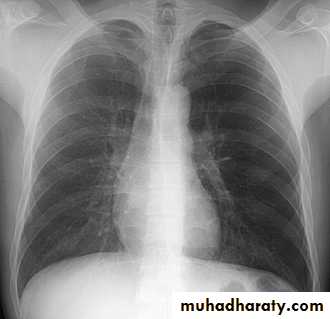

Standard views are the PA & Lateral

PA ( frontal ) VIEW LT. LATERAL VIEW

1) CXR

Parts :• 1) Lungs ( Both lung fields )

• 2) Mediastinum

• 3) Chest wall (ribs& soft tissues )

• 4) Diaphragm

• 5) HilaGood CXR = correct diagnosis